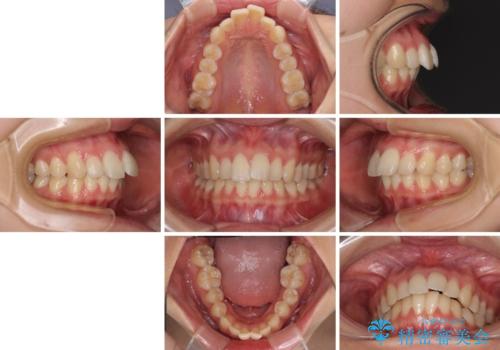

- 前歯の突出感を気にして来院された患者様です。

左右ともに奥歯の咬み合わせが上顎前突となっており、上顎前歯が飛び出している状態でした。

奥歯の咬み合わせ改善が必要であるため、マウスピース矯正より確実に達成のできるワイヤー矯正にて治療を行うこととしました。

- 矯正装置

- 審美装置